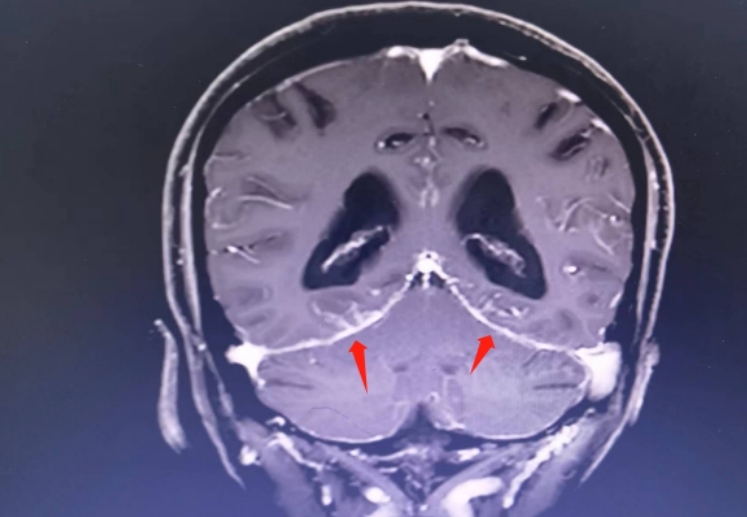

原来,一个月前韩奶奶的家人发现她突然不记得事情了,老伴被喊成哥哥,煮饭的高压锅被放到了阳台上,天天陪伴她的亲人如同路人。这一系列奇怪的言行使家里人慌了神,于是急忙将其送到湖南省脑科医院(湖南省第二人民医院)就诊。医生检查发现,造成韩奶奶失语的原因是脑袋里面长了肿瘤,不仅是脑实质的病变,还有脑膜也出现了转移,所以才造成韩奶奶不仅神经和精神出现了改变,还伴有剧烈的头痛及呕吐。

▲箭头所指为明显强化的软脑膜

肿瘤科何伟凤教授抓紧时间为其完善腰椎穿刺检查,这一查,不仅发现脑脊液的压力很高,还在脑脊液中找到了一群特殊的癌细胞,进一步作了基因检测,终于明确了肺腺癌脑转移!通过腰椎穿刺给予靶向药物治疗,联合靶向药物口服,一个疗程下来,韩奶奶身体情况迅速好转,从每天昏昏欲睡、头痛头晕中逐渐康复。3个星期后,当她再次回到温暖的家时,又拿起了熟悉的“锅铲”。

肿瘤科何伟凤医生介绍,像韩奶奶这个情况在临床工作中还不少见,关键是容易被忽视。特别是当既往没有精神病史的中老年人,一旦出现莫名其妙的精神症状时,要考虑到脑肿瘤的可能,其中一部分可能就是脑转移瘤。而最容易引起脑转移的癌症一是肺癌,其次就是女性的乳腺癌,而当合并有明显的头痛时,还要注意排查是否有脑膜转移的情况,通过磁共振等脑膜增强序列检查便能够避免漏诊。

脑膜转移癌是一个预后比较差的恶性肿瘤,一旦出现,患者的生存期会明显缩短,自然生存期一般不超过3个月。此外还要结合具体的癌种而论,就肺癌而言,因为部分非小细胞性肺癌可以有靶向药物使用,常规情况下使用标准剂量,而为了提高某些靶向药物在脑脊液中的浓度,少数靶向药物专门作了加量的研究,既确保疗效,又不至于因为加量产生大的毒副反应,就像给韩奶奶开出的药方一样,通过腰椎穿刺将化疗药物直接注入到脑脊液中,更是提高了治疗的效果。因此,韩奶奶便很快取得了明显的效果。

何伟凤医生介绍,针对脑转移瘤和脑膜转移瘤,全脑放疗加上陀螺刀精准放疗也是一种策略,特别是当脑转移的占位效应明显,头痛症状突出的时候,加上放疗能够迅速缓解头痛的症状。正是得益于上述多种手段的联合治疗,韩奶奶才能够从重病中迅速康复,重新回到正常的生活状态。